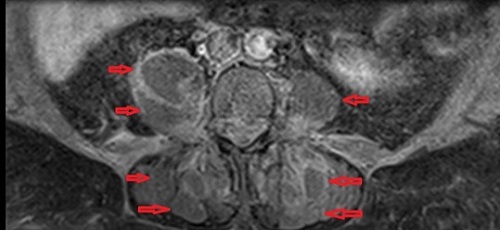

Στις εικόνες της μαγνητικής διακρίνονται τα διάφορα αποστήματα (κόκκινα βέλη) στους μύες (λαγνοψωίτες, απιοειδείς και δεξιό γλουτιαίο).

Το απόστημα του δεξιού λαγονοψωίτη καταλάμβανε ολόκληρη την έκταση του μυός. Τέλος, σημαντικό νέο εύρημα ήταν η παρουσία επισκληρίδιου εμπυήματος το οποίο κρίθηκε ότι δεν χρειάζεται χειρουργείο.